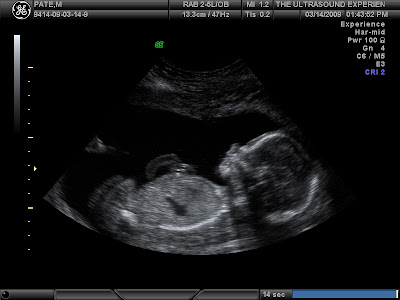

Although Megan was VERY sick for a large portion of the pregnancy thus far, things have been much better lately and there is something really cool that we did last weekend that I now would recommend to anyone – The 3D ultrasound experience which is actually what the place is called. We invited the family to come and watch because we knew we’d be told what we are having. Our tech was really nice and it was a really comfortable experience. Right away she was able to tell the results…It’s a GIRL! We are so stoked.